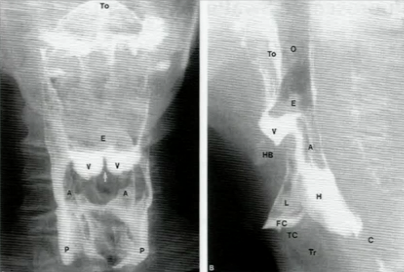

What structures are indicated in the image?

To = base of tongue, E= epiglottis, V= volleculae, A= aryepiglottic folds, P= pyriform recesses. H= hypopharynx, L = larynx, HB = hyoid bone